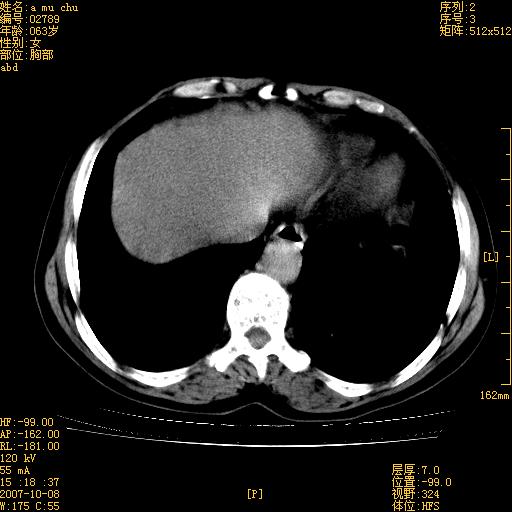

以下是引用王维浦在2007-10-17 21:02:00的发言:[br]胆囊增大,囊壁明显不规则增厚,邻近肝组织浸润,肝内外胆管无扩张。诊断:胆囊ca;[br]胰头软组织肿块影,考虑是由转移肿大的胰后淋巴结、没有肠道准备的十二指肠及胰头共同形成。[br]

以下是引用zhangzexing在2007-10-18 7:13:00的发言:[br]支持胰头占位,慢性胆囊炎. 2.肝左叶前外侧段占位,血管瘤?建议增强

以下是引用影像实习生在2007-10-17 19:49:00的发言:[br]支持胰头占位,慢性胆囊炎. 2.肝左叶前外侧段占位,血管瘤?建议增强.

以下是引用刘振江在2007-10-17 19:42:00的发言:[br]没有增强,胰头癌?胆囊及肝左叶占位?